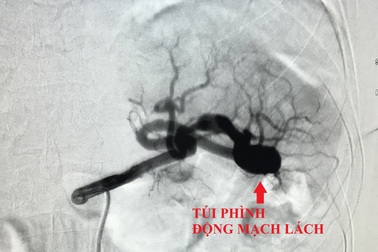

Đau bụng âm ỉ, coi chừng mắc bệnh lý nguy hiểmNhập viện vì đau bụng âm ỉ, nữ bệnh nhân được bác sĩ phát hiện bị phình động mạch lách dọa vỡ. Bằng kỹ thuật can thiệp nội mạch, vị trí túi phình được bác sĩ gây tắc giúp người bệnh qua nguy kịch.